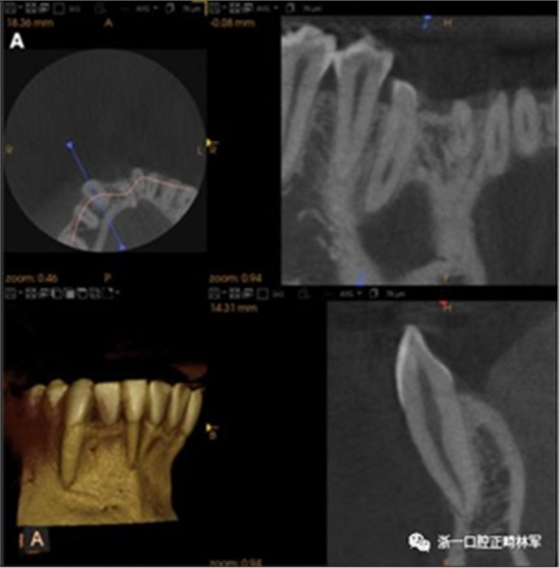

臨床檢查顯示固定保持器完好,弓絲沒(méi)有斷裂(圖13)。在下頜右側(cè)中切牙唇側(cè)和鄰近側(cè)切牙的舌側(cè)注意到有牙齦退縮。這些牙齒在退縮方向上存在顯著的扭矩差異。下頜的左側(cè)尖牙頰側(cè)錯(cuò)位,而右側(cè)尖牙舌側(cè)傾斜。三維射線照片證實(shí)了下頜右側(cè)尖牙面?zhèn)妊啦酃菃适?,右?cè)中切牙的喪失程度較輕。右側(cè)側(cè)切牙根也從舌側(cè)骨面上扭轉(zhuǎn)出來(lái)(圖14)。

圖14.三維立體圖像:A,面部和B,切牙根部的舌側(cè),剛?cè)〕龉潭ㄉ鄠?cè)保持器后。